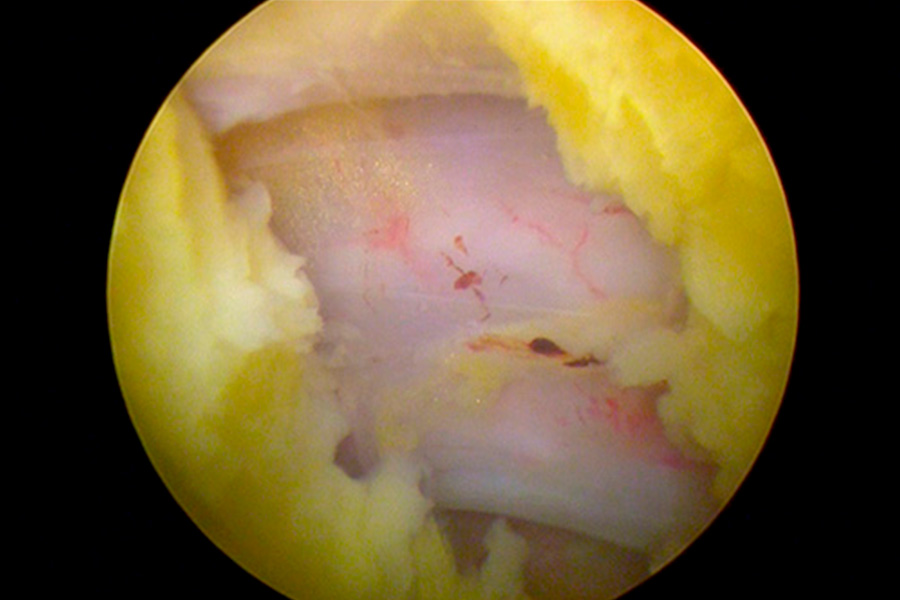

Caso clínico: endoscopia de columna multinivel L4L5 y L5S1

Los síntomas que presentaba el paciente eran dolores acentuados en las piernas, claudicación a la marcha y calambres y hormigueos en las piernas.

Durante la intervención quirúrgica, se abordarán los dos niveles mediante la técnica de endoscopia de columna.